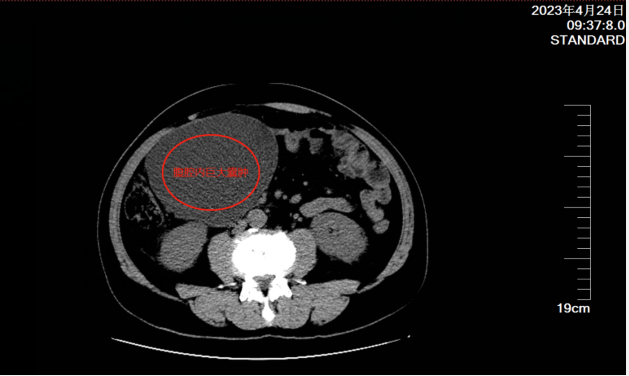

入院后,检查确定是右中腹部腹腔内囊性病变,医生初步判断他得了肠系膜肿瘤,需要手术治疗。

4月26日,该院普外科为他实施了“肠系膜肿物切除术”,术中见腹腔有一巨大囊肿,大小约13*13*15厘米,质地软,有波动感,与周围组织轻度粘连。继续探查发现囊肿根部位于结肠系膜处、结肠动脉旁。